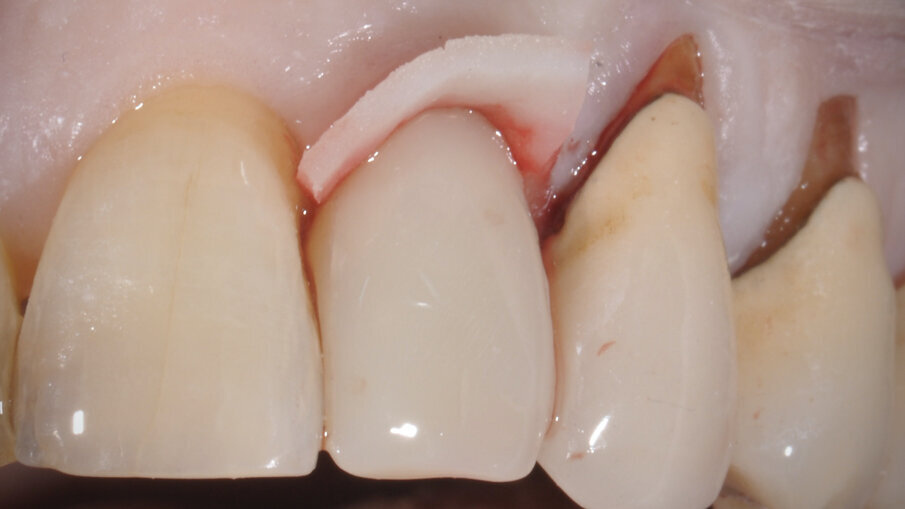

È stato inserito un impianto Straumann BLX 3.75 mm di diametro per 12 mm di lunghezza, con superficie SLActive seguendo l’asse protesico ideale (Figg. 4, 5). Avendo conseguito una stabilità primaria eccedente i 35 N/cm è stato realizzato un restauro provvisorio avvitato in composito su componente in Titanio da provvisori. Nonostante una sostanziale congruità della forma del provvisorio con la parte superficiale dell’alveolo, è stata utilizzata una matrice dermica suina (Botiss Mucoderm) allo scopo di sigillare il gap presente tra provvisorio e bordo mucoso dell’alveolo. Tale matrice, opportunamente sagomata e forata in modo da essere stabilizzata dal provvisorio stesso, è stata posizionata in modo da non rimanere esposta al cavo orale. Non sono state necessarie suture (Figg. 6-8).

Fig. 6_Matrice dermica suina forata per la stabilizzazione mediante provvisorio.

Fig. 7_Provvisorio in sede con matrice dermica suina esposta.

Fig. 8_Provvisorio in sede con matrice dermica inserita sotto i tessuti molli.